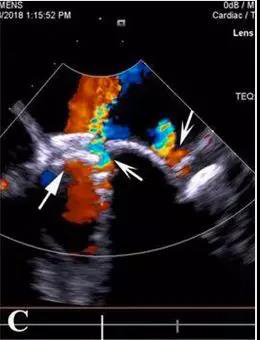

然而,封堵器释放后,发现封堵器伞间残余漏(宽仅2mm),就是说“铆钉”的缝隙里仍有血漏过。高速通过缝隙的血流受剪切力影响,造成血细胞破坏,患者术后严重溶血、贫血和血红蛋白尿,白细胞高,血小板低,肝肾功能降低,黄疸,需要间断输血维持。

怎么办?再次开胸体外循环手术患者难以耐受,可能意味着死亡,风险更大。而再次经胸封堵术需要去堵“铆钉”间的缝隙,漏口小,对医生的难度大、风险大。有导丝无法通过漏口、捅掉以前植入的封堵器,术后仍然有残余漏、溶血等风险。顶着巨大的压力,李红昕和郭文彬带领的医疗团队经过认真的讨论、分析,决定依据心尖入路比较直的特点,改经左胸-心尖途径去封堵“铆钉”间的缝隙。术中,他们利用自主发明的直中空探条输送系统,成功将导丝送过两个伞盘的间隙,分别再次植入一枚特质封堵器,共4枚,完全封堵住了MPVL。术后患者血红蛋白尿、贫血、黄疸消失,肝肾功能恢复正常,痊愈出院。

经胸MPVL封堵,全部在三维超声引导下操作,解剖图像清晰,患者和医务人员不接触X线和造影剂;中空探条输送系统短,操作灵活,封堵MPVL成功率高。有关该技术的文章已于今年发表于世界顶级心胸外科杂志《Ann Thorac Surg》上。三位患者的成功表明:经右胸或左胸途径微创封堵MPVL能克服传统介入治疗的不同难点,已逐步走向成熟,成为治疗二尖瓣瓣周漏的又一利器,为患者解除了再手术痛苦,为心外科医生解除了后顾之忧。